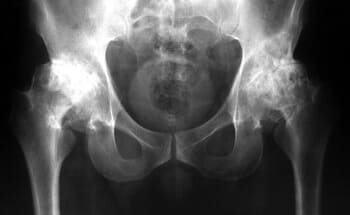

দুই বছর আগে আমি প্রথম আমার হাঁটু এবং নিতম্বে হালকা ব্যথা অনুভব করেছি। ব্যথা তীব্র ছিল না, তাই আমি এটিতে খুব বেশি মনোযোগ দিইনি... দেখা যাচ্ছে যে জয়েন্টের রোগগুলি খুব বিপজ্জনক এবং অবিলম্বে চিকিত্সা করা উচিত, আমার মতো অপেক্ষা করা উচিত নয়। একদিন আমার হাঁটুতে হালকা কিন্তু তীক্ষ্ণ ব্যথা হয়েছিল, এবং আমার নিতম্বের জয়েন্টটি গুরুতরভাবে আঘাত করতে শুরু করেছিল, এবং আমি ভেবেছিলাম যে কিছুই ভুল ছিল না, এটি চলে যাবে, যেমন এটি সাধারণত হয়। আমি ওষুধ ও মলম কিনে ব্যবহার শুরু করলাম। এক সপ্তাহ বা তার পরে, আমার অবস্থা তীব্রভাবে খারাপ হয়ে যায়, ব্যথা অসহ্য হয়ে ওঠে, আমার নিতম্বের জয়েন্টে তীব্র ব্যথা শুরু হয় এবং আমি প্রথমবারের মতো ডাক্তারের কাছে যাওয়ার সিদ্ধান্ত নিয়েছিলাম। তারা আমাকে একটি রোগ নির্ণয় দিয়েছে যা সস্তা ছিল না এবং আমার ডাক্তার পরীক্ষার ফলাফল দেখে আমাকে বলেছিলেন:

"আপনি আগে উপসর্গ উপেক্ষা কেন? আপনার অস্টিওআর্থারাইটিস আছে! অস্টিওআর্থারাইটিস, আপনি যদি অক্ষম হতে না চান তবে আপনাকে নিতম্ব এবং হাঁটু অস্ত্রোপচার করতে হবে!

হাঁটু এন্ডোপ্রোস্টেসিস, ছবি

হাঁটু জয়েন্টের তরুণাস্থির উপর অস্টিওআর্থারাইটিসের প্রভাব।